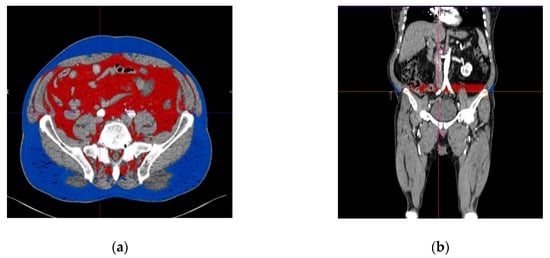

To determine the volume of the subcutaneous and visceral adipose tissue at the whole length of the chosen common iliac artery, we used the function of automated interpolation of contours to create the separation line on the anterior and posterior abdominal muscles at the whole length of the vessel, as presented in Figure 3. The volume of the subcutaneous and visceral adipose tissue was then determined automatically and displayed together with the ratio between them. Figure 4 illustrates a diagram of the image postprocessing steps.

Figure 3.

Subcutaneous and visceral adipose tissue determined with angio CT (computed tomography angiography), measured at the level of the origin of the right common iliac artery. (a) Transverse view, (b) longitudinal view. The visceral adipose tissue is represented in red, while the subcutaneous adipose tissue is represented in blue.